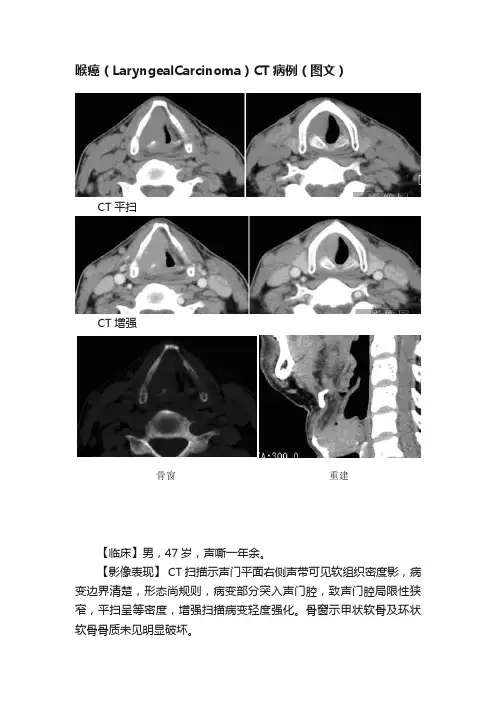

喉癌(LaryngealCarcinoma)CT病例(图文)

CT平扫

CT增强

骨窗重建

【临床】男,47岁,声嘶一年余。

【影像表现】 CT扫描示声门平面右侧声带可见软组织密度影,病变边界清楚,形态尚规则,病变部分突入声门腔,致声门腔局限性狭窄,平扫呈等密度,增强扫描病变轻度强化。

骨窗示甲状软骨及环状软骨骨质未见明显破坏。

【诊断】(喉腔)中-低分化鳞癌,侵及甲状软骨表层。

(病理确诊)